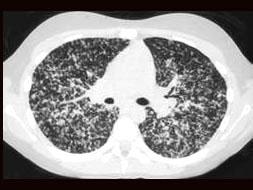

问题 女性,19岁,低热,盗汗,乏力,咳嗽1月余,CT检查如图,请选出最可能的诊断 ( )

选项 A、矽肺 B、大叶性肺炎 C、弥漫型肺癌 D、粟粒型肺结核 E、间质性肺炎

答案 D